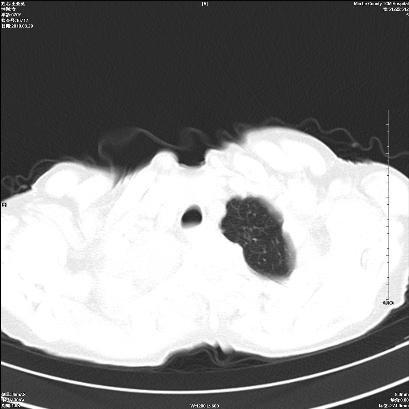

标题: CT25424:女性,70岁,胸闷、咳嗽月余。 [打印本页]

右肺上叶支气管开口阻塞,上叶呈不均匀致密影,右肺中下叶内见斑片状密度增高影,上叶见钙化点,纵隔内见钙化淋巴结,桶状胸,右下肺动脉增粗,残根征,意见:1.右肺中心性肺癌;2.右肺陈旧性结核;3.肺心病。

ct所见:右肺上叶肺不张,呈软组织密度影向肺门区聚拢,其内可见含气段支气管及细支气管影,病灶内尚可见钙化结节。右肺上叶支气管狭窄,段支气管壁可见钙化。右肺下叶背段、右肺中叶见不规则小片絮状影及纤维条索影,形态较僵硬。右肺中叶胸膜旁可见多个小结节影。纵膈内见钙化淋巴结。

分析:右侧胸廓及右肺体积缩小,说明病变时间比较长了,应该是有数年的时间了,如果是短期内出现的肺不张,只会引起纵膈向患侧移位,而不会引起胸廓的塌陷。不张的肺组织内可见含气支气管影,说明右肺上叶支气管没有完全中断,只是狭窄。右肺中叶、下叶散在不规则病灶,部分呈纤维化改变。纵膈内的淋巴结大部分钙化。因此,本例给我的感觉良性病变的可能是大。

结论:考虑右肺上叶支气管内膜结核合并右肺上叶肺不张;右肺中叶、下叶陈旧性肺结核改变。